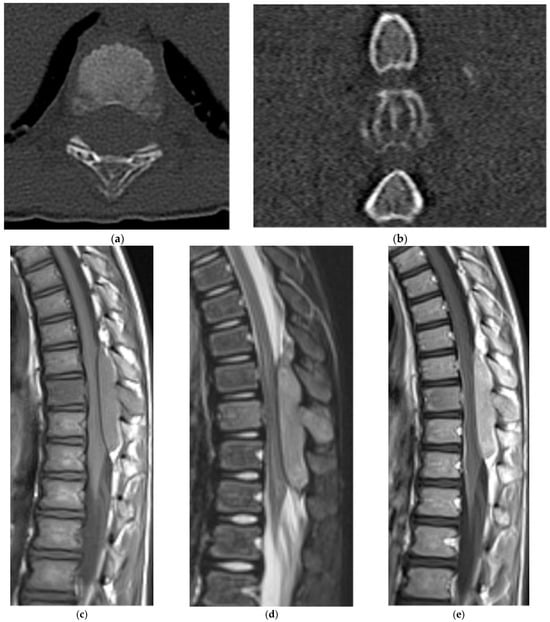

2.5.1. Hemangioma

2.5.2. Aneurysmal Bone Cyst